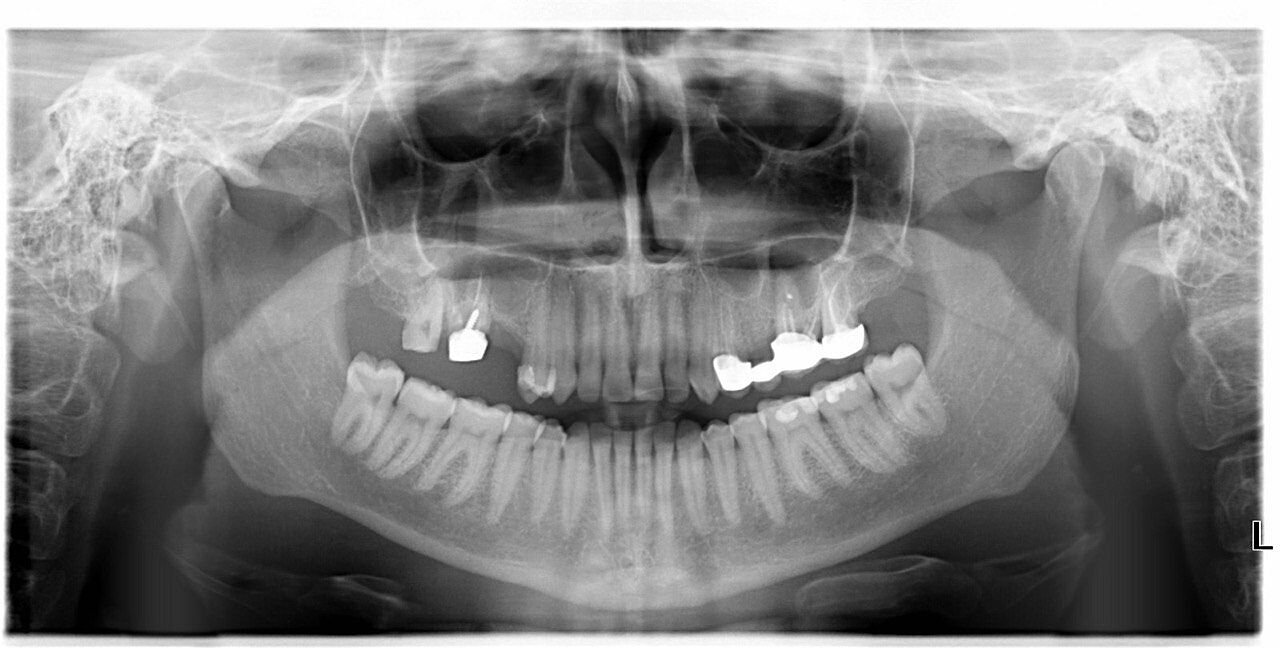

Все эти дни хожу мучаюсь от боли, сначала думала десна, полоскала разведенной антисептической жидкостью которую врач назвал, десна вроде заживают,но боль ничуть не утихла, на таблетках( кормлю грудью, поэтому позволяю себе только парацетамол). Вчера нашла клинику не далеко от себя, сделала панорамный снимок, но к врачу не попала( запись, ближайшее окошко в четверг), отправила снимок к врачу своему он" инфекции не видно, скорее всего болит живой зуб,посмотрим, когда ко мне попадете). На днях поеду к нему,но мучаюсь в сомнениях,так ли он компетентен, вдруг он что то неправильно сделал, что уже какой день боль такая. Посмотрите кто разбирается пожалуйста, болит вся верхняя правая сторона( крайние два верхних правых зуба( на снимке это вверхние два левых), так что боль до глаза доходит, в первые два дня стреляло даже в виски).

Если зуб живой и без временной коронки - да, может болеть и от воды. Если боль продолжается после прекращения действия раздражителя, то и пульпит может быть. Неживой зуб тоже восторга не вызывает: 1. качество эндодонтического лечения 2. наличие штифта с отклонением от оси канала 3. есть вопросы к качеству твердых тканей зуба под пломбировочным материалом ( надеюсь доктор снимал пломбу полностью и визуально все видел). И ненормально было начинать протезирование без снимков

В семерке может быть пульпит, в шестом периодонтит. Врач не компетентный.